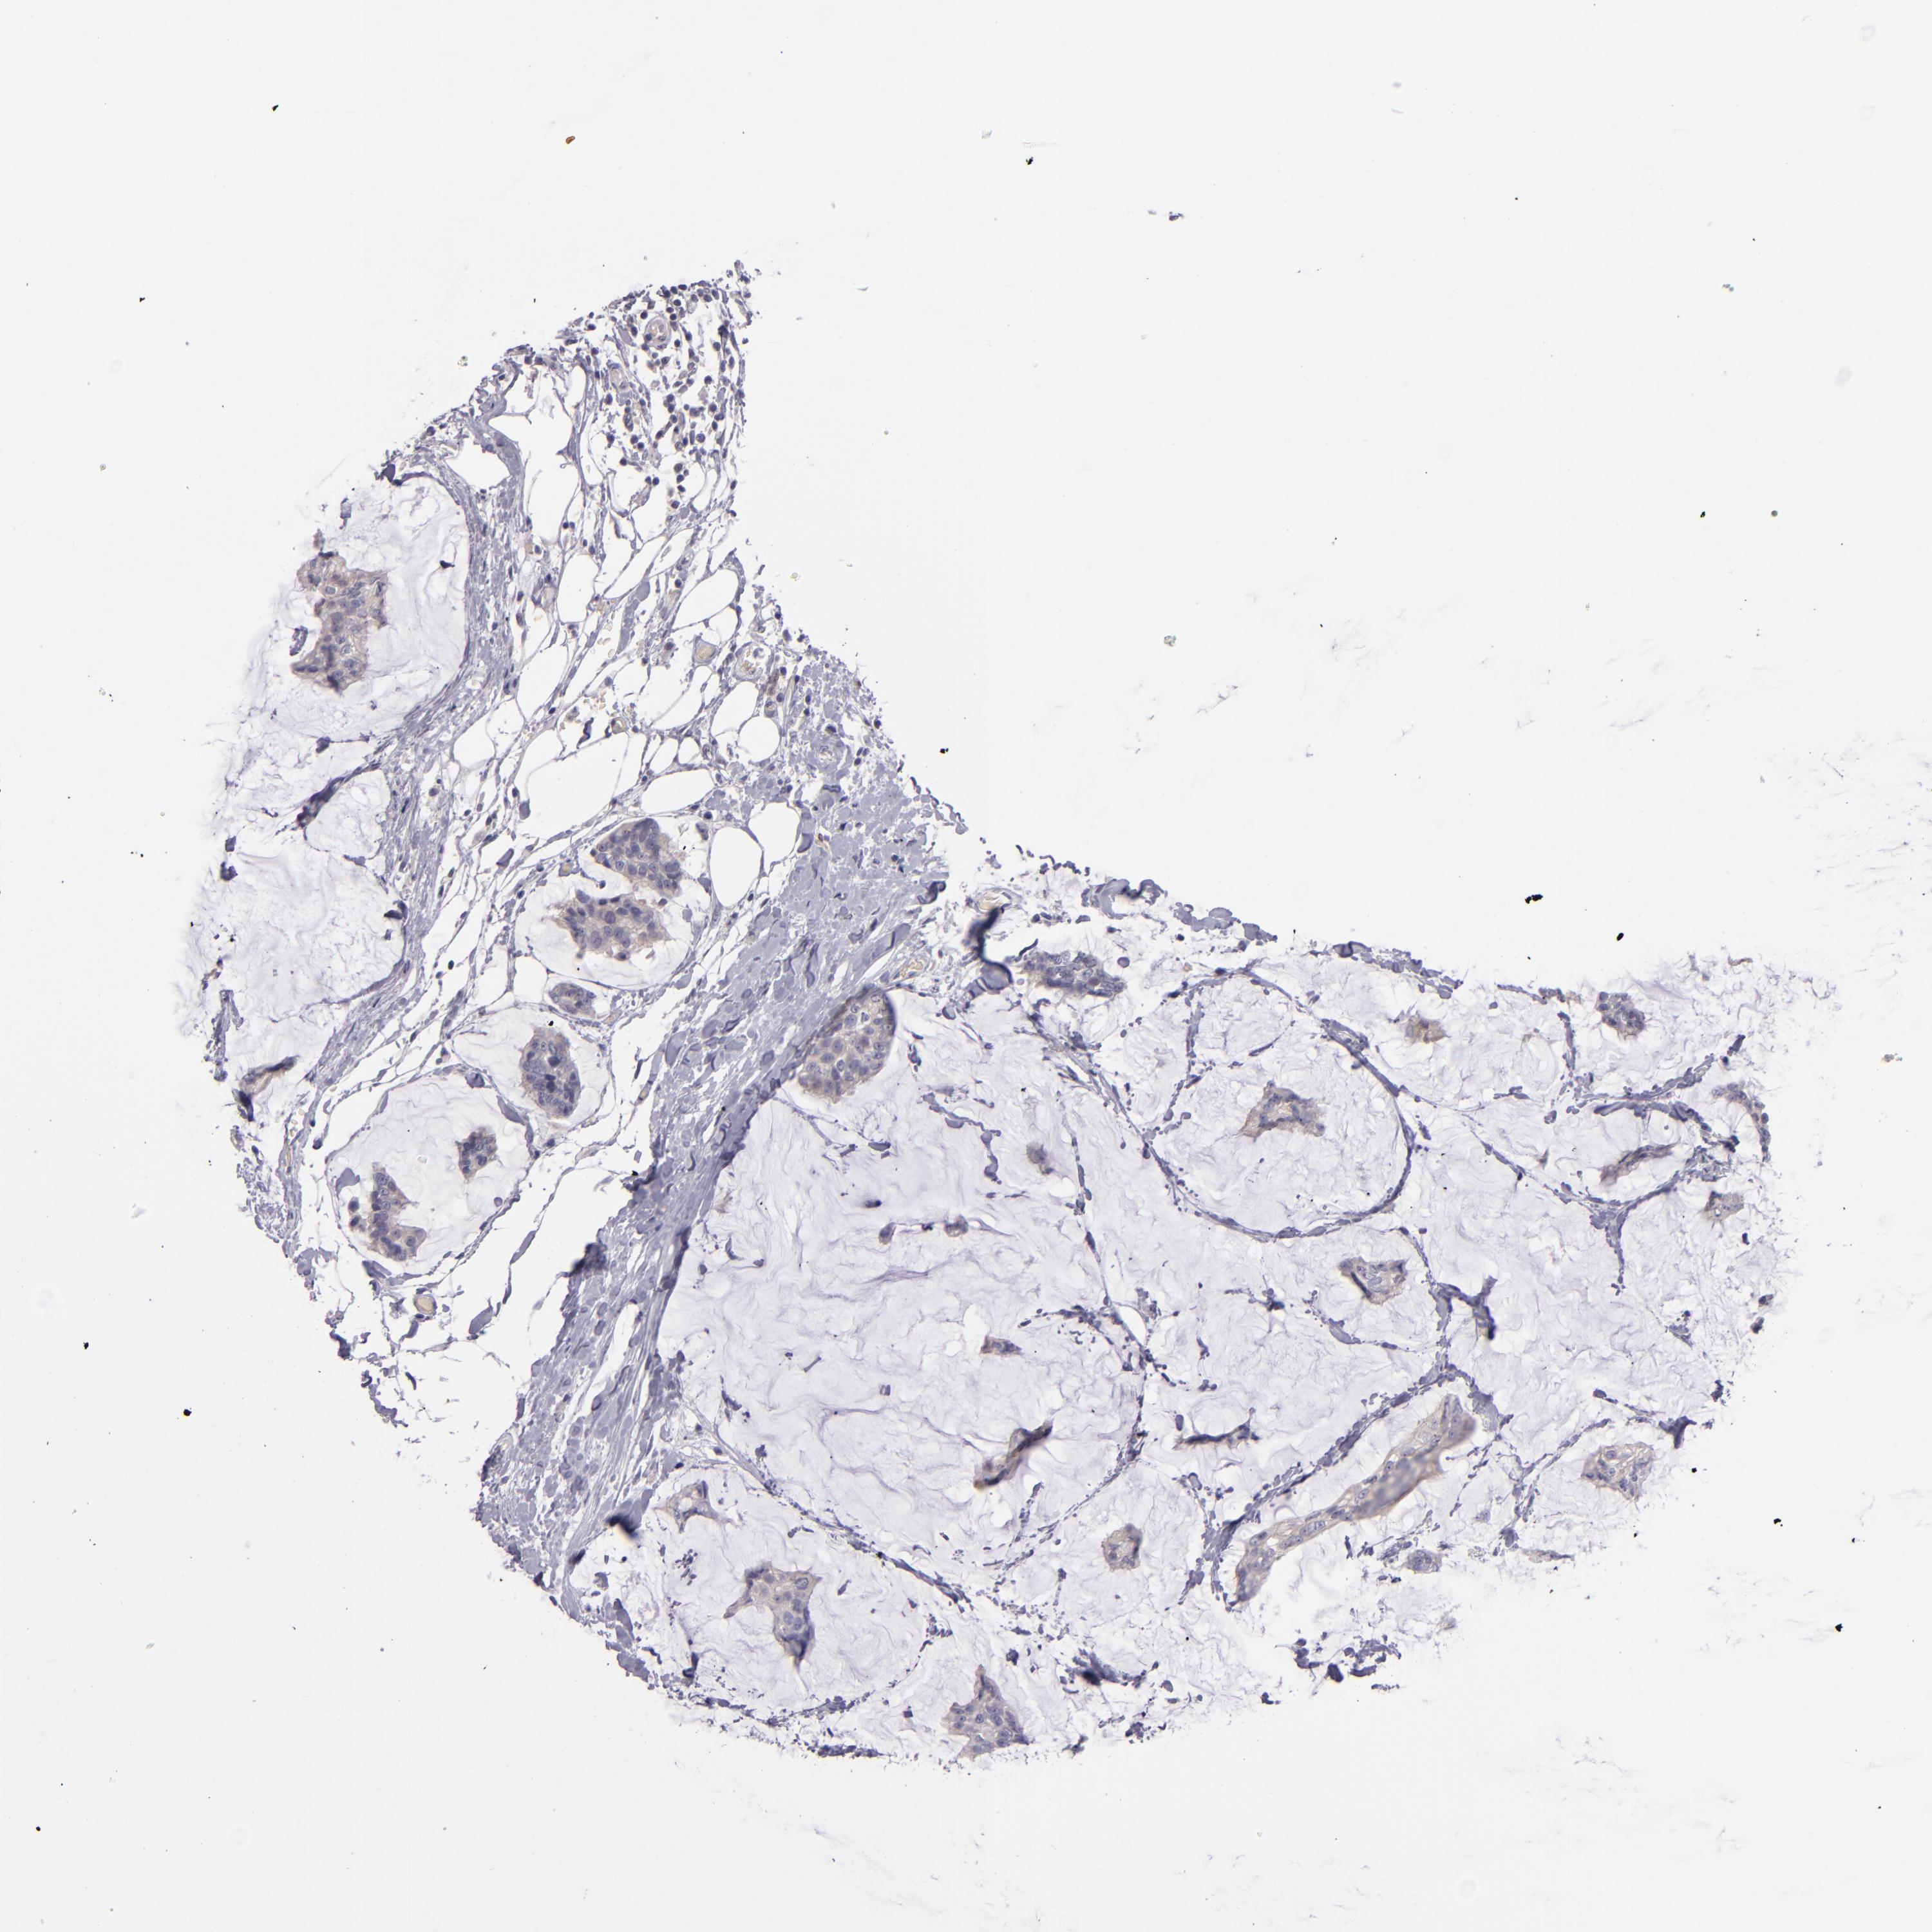

BRCA TCGA BRCA VALIDATION PROTEIN EXPRESSION

ANTIBODIES

AND

VALIDATION